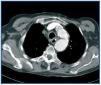

Therefore, a chest CT was performed with contrast. This revealed, in the aortic arch, distal to the supra-aortic trunks, a poststenotic dilatation of a maximum of 3.7cm in diameter, compatible with aortic coarctation (Figure 2).

Figure 2.